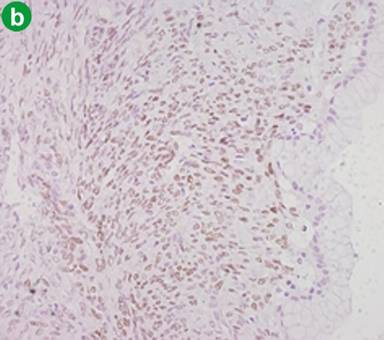

Macroscopically, the examination of the specimen showed a cystic lesion measuring 40 mm of maximum diameter. The cut surface demonstrated a unilocular cystic pattern with smooth and white inner walls, containing viscous whitish mucin. The cyst showed a peripheral pattern of growth, without communication with the pancreatic ductal system. The remaining parenchyma was normal and the transection margin was 20 mm far from the mass. Microscopically, the cystic lesion showed two distinct components: a mucinous epithelial layer showing low-grade dysplasia and an ovarian-type stroma (according to WHO 2010 [3]). Immunohistochemically, the stromal layer was positive for estrogen, progesterone and calretinin receptors (Figure 2). According to these findings, the cystic lesion was diagnosed as a MCN having ovarian stroma of the pancreas; lymph nodes (n=6) were negative.

Figure 2. a. Microscopically (hematoxilin-eosin x100), an ovarian type stroma layer, that appears as a band of densely packed spindle cells, is covered by a mucinous epithelial low grade dysplasia layer. b. Immunohistochemical analysis (x100) of the ovarian type stroma, showed expression of receptors for estrogen. |